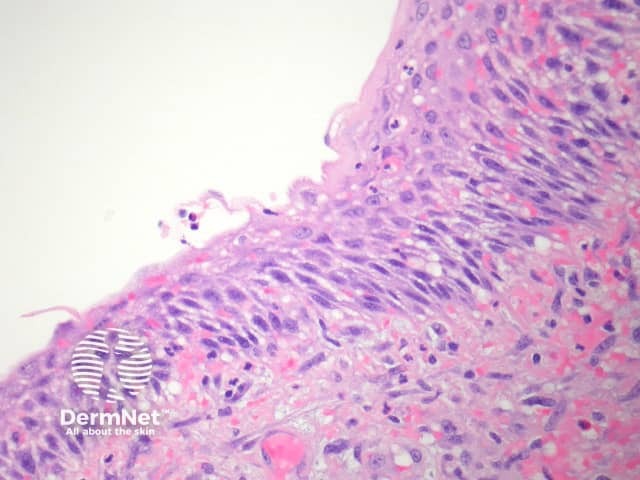

A branchial cleft cyst is often surrounded by lymphoid tissue (figure 1). The lining of the cyst is usually a stratified squamous epithelium (figure 2). The lining may also be a columnar ciliated epithelium. Often there are marked inflammatory changes and the epithelium overlying the lymphoid tissue is attenuated/absent (figure 3). Smooth muscle is rarely seen in the wall. Mucous glands and cartilage may also sometimes be seen in the wall.

Figure 2